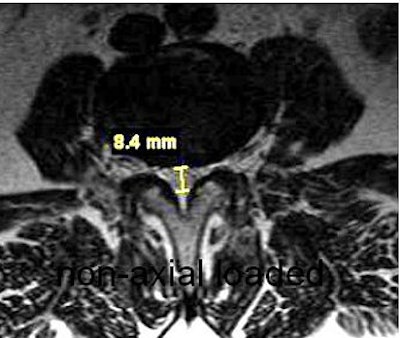

| Same patient as above. Top, transaxial T2-weighted image showed left L4 spinal nerve root compromise with axial loading (below). |

Willen and Danielson have also shown that axial-loaded imaging, during recumbent MRI or CT, simulates weight-bearing forces in the lumbar spine, provoking narrowing of the central spinal canal and neural foramina, and increasing the diagnostic accuracy of dynamic spinal stenosis. Dynamic stenosis has been defined in literature as a change in the cross-sectional dural sac area of greater than 15 mm² resulting in a decrease in the dural sac area to less than 75 mm (Spine, December 1, 2001, Vol. 26:23, pp. 2607-2614; Acta Radiologica, November 1998, Vol. 39, 6, pp. 604-611; Spine, December 1, 2001, Vol. 26:23, pp. 2601-2606).

Willen and Danielson's group found that 79% of patients with combined low back and leg symptoms experienced a significant reduction of the dural sac cross-sectional area during axial compression; 35% of patients passed the borderlines for relative stenosis (100 mm²) or absolute stenosis (75 mm²); 36% of patients experienced deformation of the dural sac during axial compression; and 13% of patients experienced a narrowing of the lateral recess during axial compression (Spine, December 15, 1997, Vol. 22:24, pp. 2968-2976).